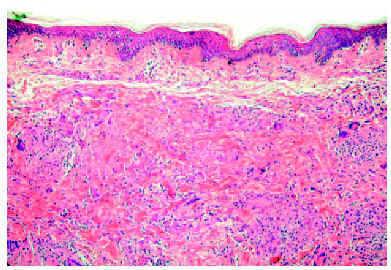

Se tomaron varias biopsias de diferentes lesiones cutáneas del tronco y las extremidades, que mostraron un cuadro similar en todas ellas de granulomas en la dermias superior y media (fig. 3). La extensión de los granulomas varió según las piezas. Los granulomas eran principalmente pequeños y bien definidos, y contenían células epitelioides y células gigantes multinucleadas. Había pocos linfocitos, de aspecto normal. Algunos granulomas estaban formados principalmente por células gigantes con numerosos núcleos (fig. 4), y algunas células gigantes contenían cuerpos asteroides. La epidermis estaba adelgazada y aplanada, y no había inflamación granulomatosa en la zona subepidérmica ni epidermotropismo. Se observaban muy pocas fibras elásticas, así como fagocitosis de las fibras elásticas por las células gigantes. No se observó fagocitosis de linfocitos.

Fig. 3.--Biopsia del muslo que no muestra todavía signos de cutis laxa. Se aprecian granulomas sarcoides en la dermis media con células epitelioides, células gigantes y un rociado de linfocitos. (Hematoxilina-eosina, x25.)

Fig. 4.--Detalle de un granuloma con numerosas células gigantes multinucleadas. (Hematoxilina-eosina, x200.)